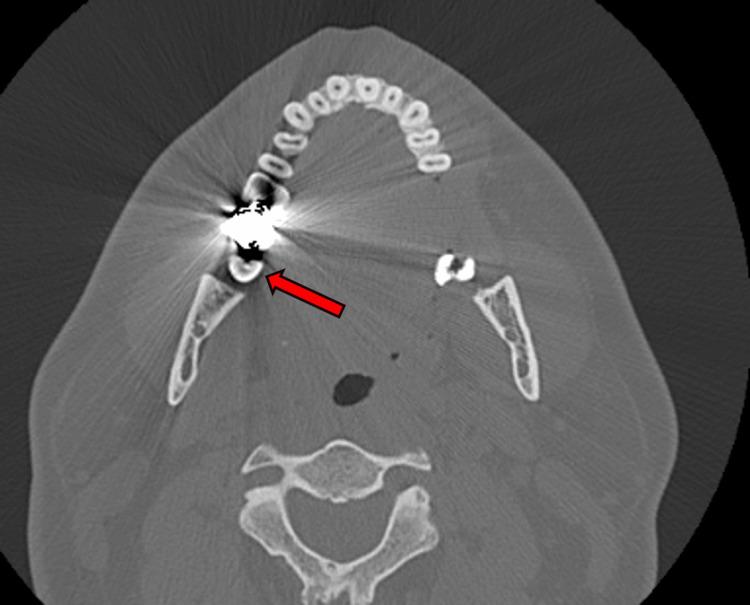

黄甲综合征(YNS)是一种罕见的疾病,其特征为三联征症状:淋巴水肿、指甲变黄和呼吸道表现。它常与慢性咳嗽、支气管扩张、胸腔积液和慢性鼻窦炎等病症相关。尽管其确切病因尚不清楚,但据信淋巴引流受损在其发病机制中起核心作用。YNS主要影响50岁以上的人群,且没有明确的治疗方法,不过一些病例可能会部分缓解或自发缓解。在本报告中,我们介绍了一名35岁左右的男性病例,他有持续咳嗽、鼻窦充血、指甲变黄变形和淋巴水肿的病史一年。包括影像学和肺功能测试在内的广泛检查未发现明显的肺部异常。该患者接受了多轮治疗,包括抗生素、抗真菌治疗、吸入和全身性皮质类固醇以及指甲护理方案,但所有这些治疗均未能有效缓解他的症状。进一步评估,包括牙科影像学检查,发现了牙源性脓肿。拔除感染牙齿后,患者的症状,包括指甲变黄和鼻窦问题,得到了显著且逐渐的缓解。该病例强调了在YNS患者的检查中考虑继发性病因(如牙科感染)的重要性,特别是在标准治疗未能产生改善效果时。据我们所知,这是第一例报告的将牙脓肿确定为YNS潜在病因的病例。YNS与多种全身性疾病有关,包括自身免疫性疾病、甲状腺功能障碍、肾病综合征和恶性肿瘤,但此前尚未记录到与牙脓肿的关联。该病例强调了对YNS潜在促成因素进行全面评估的迫切需求,特别是在不符合典型人口统计学特征的年轻患者中。它还强调了及时处理继发性感染的重要性,这可导致此类病例的显著临床改善。通过说明YNS的一种罕见表现,该病例进一步深入了解了该综合征的复杂性以及牙源性感染在其发展中的潜在作用。